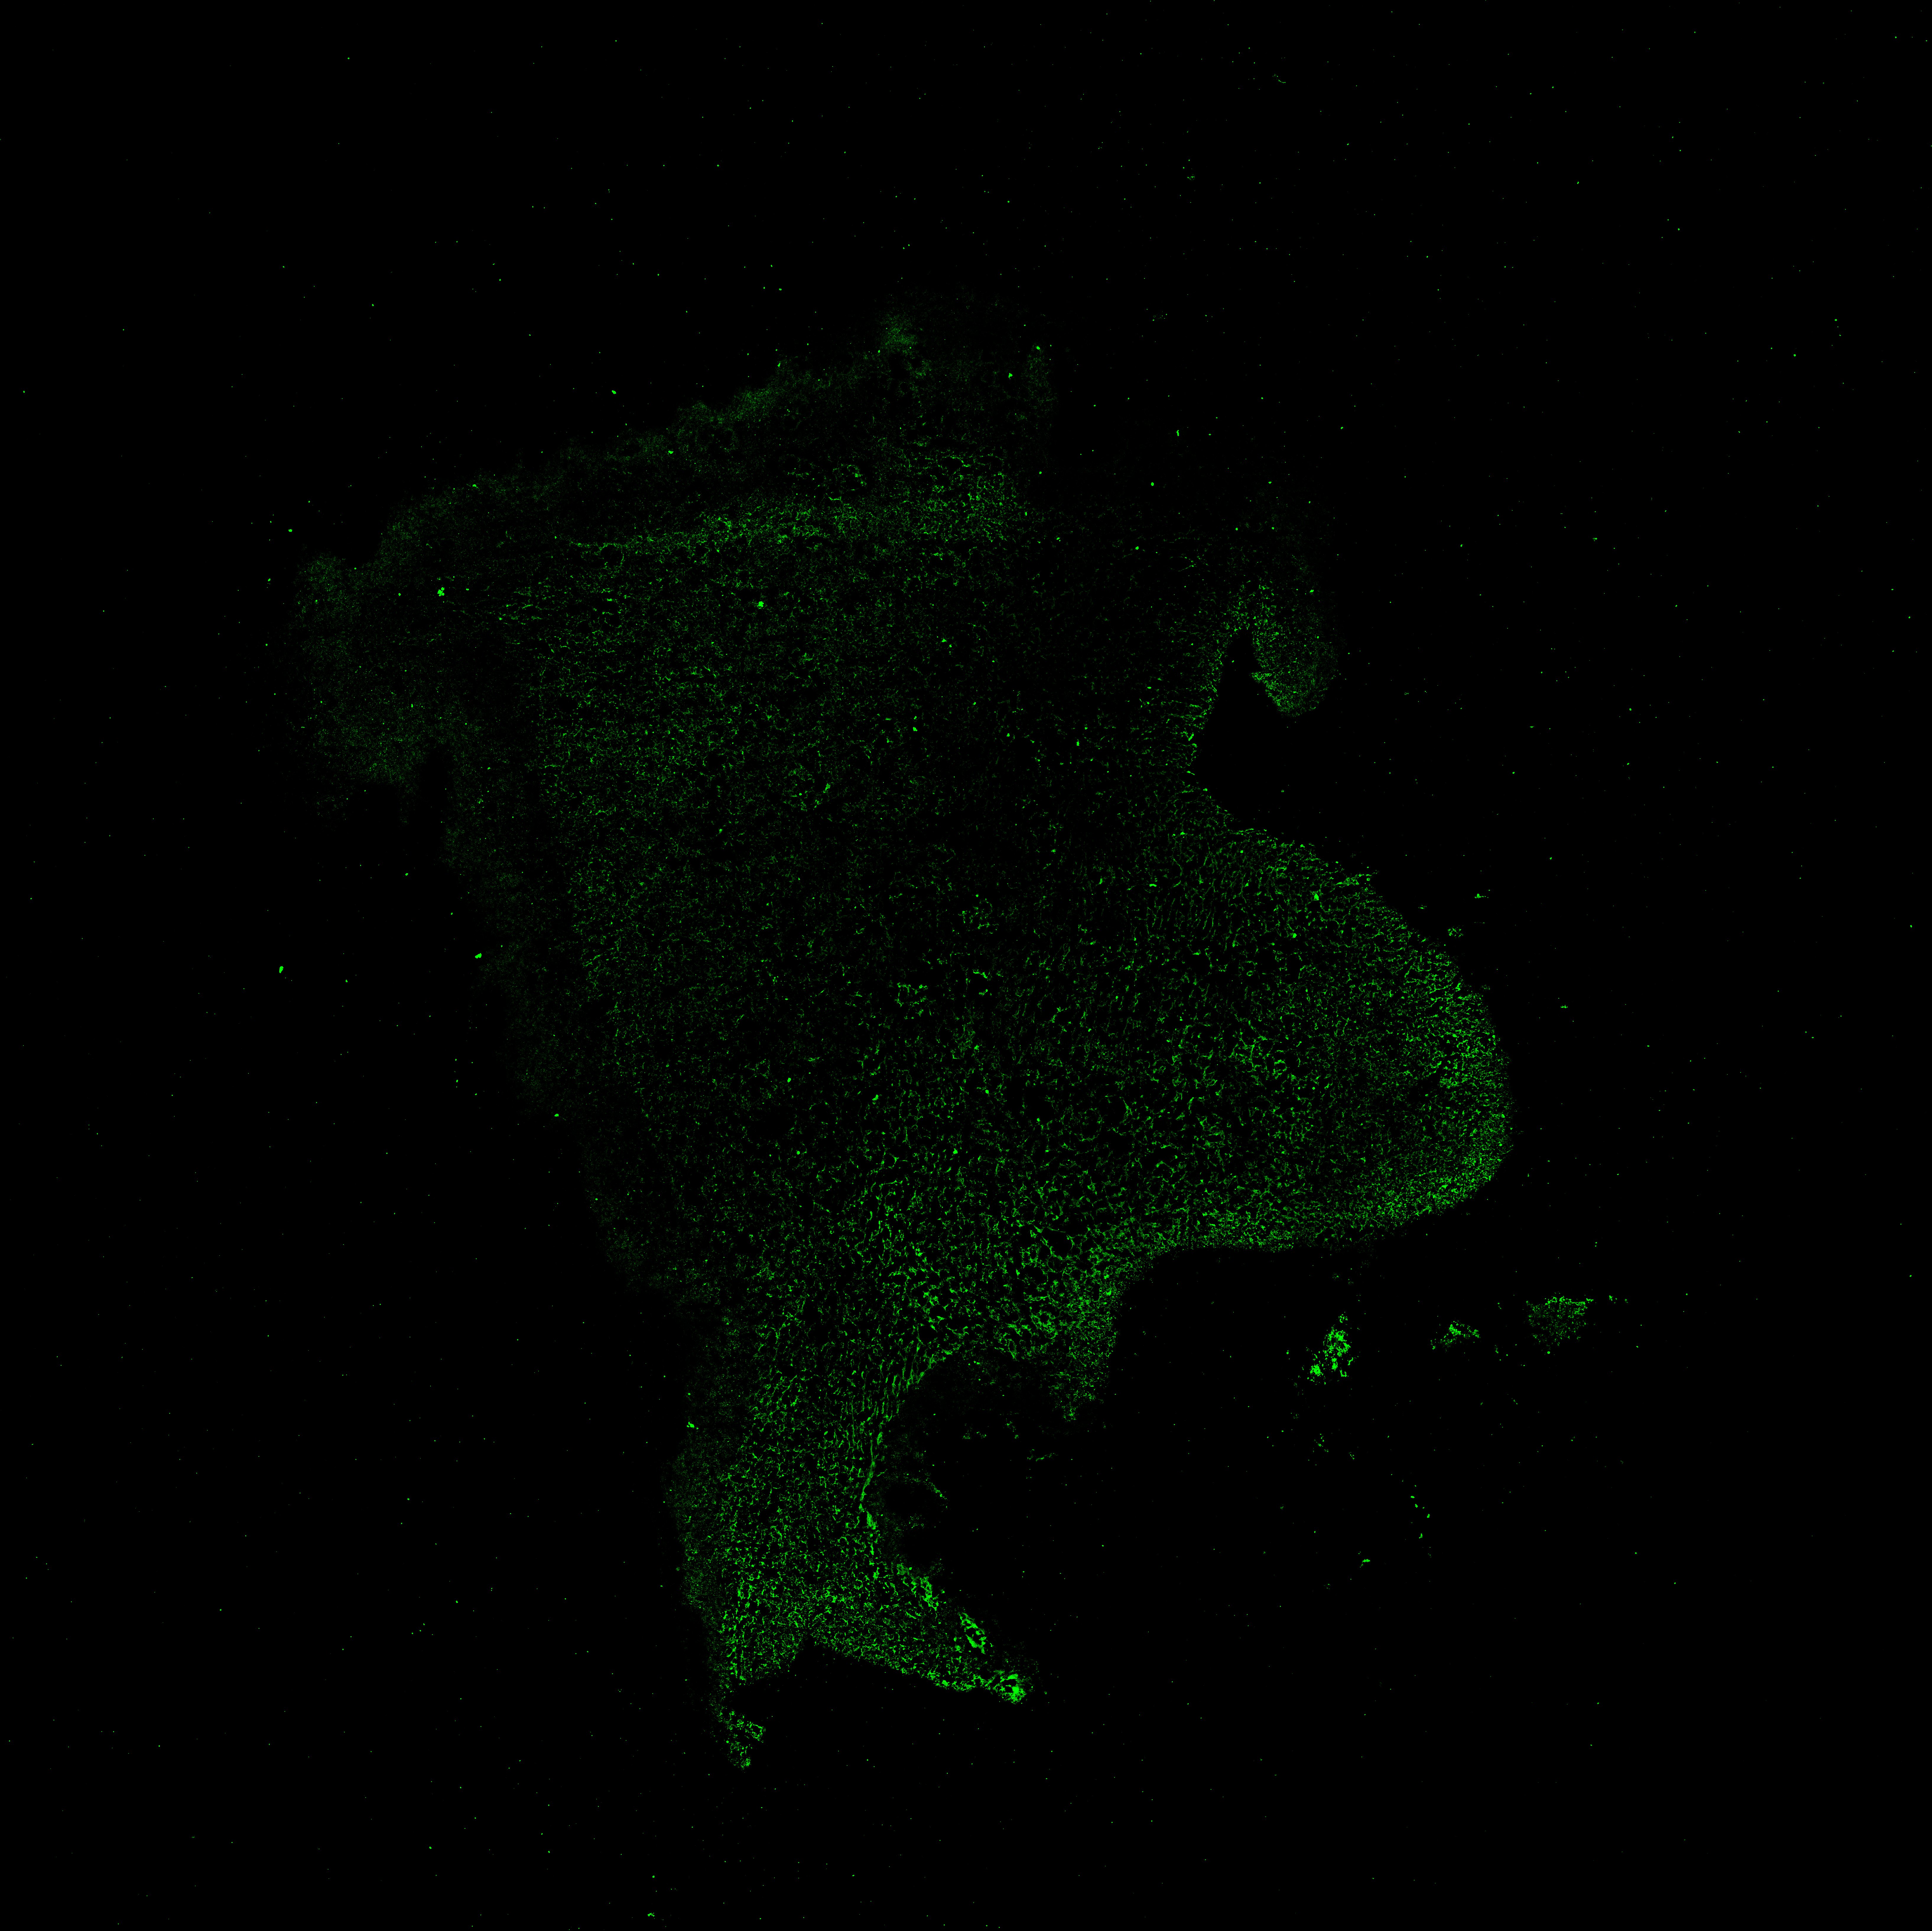

MAP2

11PCW human midbrain

SOX2

13PCW human midbrain

15PCW human midbrain

17PCW human midbrain

19PCW human midbrain

22PCW human midbrain